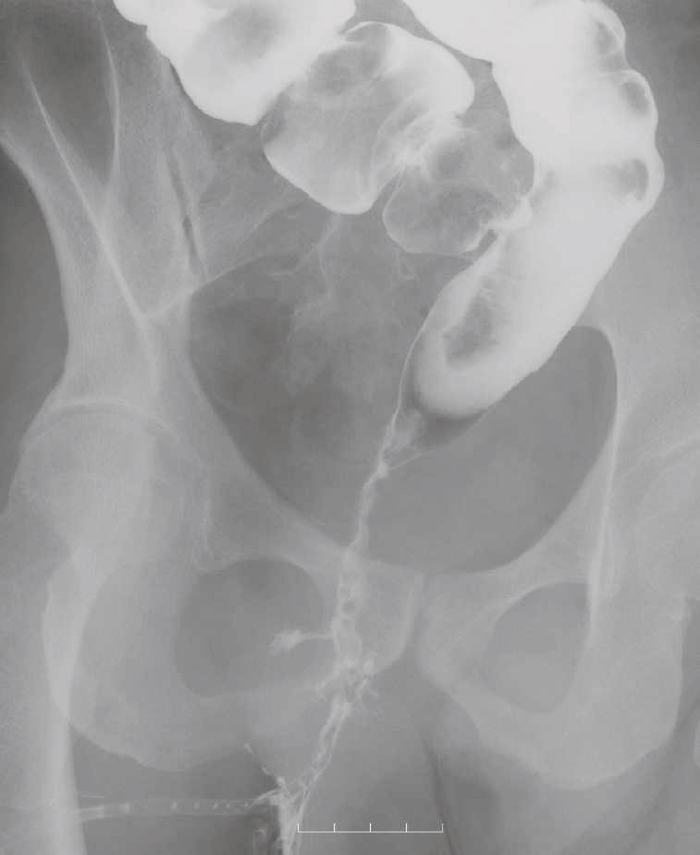

診断時のMRIでは直腸下部壁内から周囲にhigh intensity areaが拡がり,右側には痔瘻の瘻管を認めた。high intensity areaは前方で前立腺や陰茎海綿体付近まで広がっていた。

図42 注腸造影検査

注腸造影検査では,直腸は狭小化しており,痔瘻に続く,瘻管が描出された。

CTではMRIと同様に広範囲のhigh density areaがあり,癌と炎症が波及した領域の区別がつかず右側方領域にリンパ節腫大を認めた。